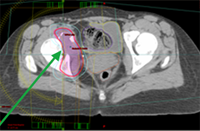

Radiosurgery plan targeting the pelvic tumor and sparing the pelvic organs.

After completion of radiosurgery: complete resolution of pain and the focus of breast cancer in the right hip, with interval healing of pelvic bone (green arrow). Brown arrow points to normal bladder and pelvic organs.